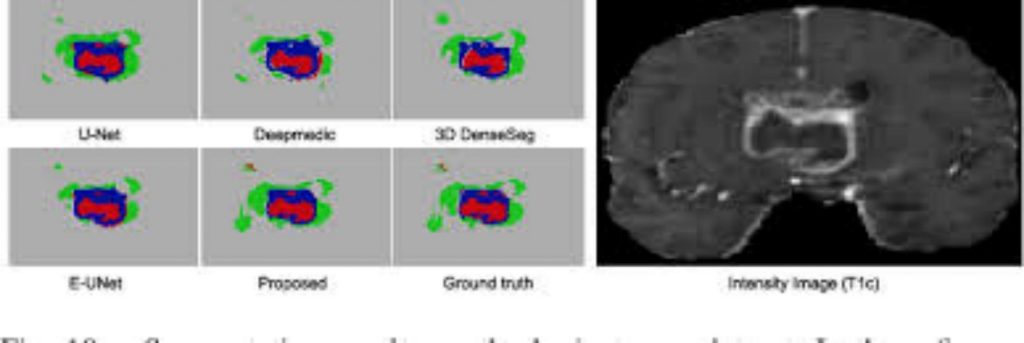

Automatic image segmentation is an essential step for many medical image analysis applications, include computer-aided radiation therapy, disease diagnosis, and treatment effect evaluation. One of the major challenges for this task is the blurry nature of medical images (e.g., CT, MR, and microscopic images), which can often result in low-contrast and vanishing boundaries. With the recent advances in convolutional neural networks, vast improvements have been made for image segmentation, mainly based on the skip-connection-linked encoder-decoder deep architectures. However, in many applications (with adjacent targets in blurry images), these models often fail to accurately locate complex boundaries and properly segment tiny isolated parts. In this paper, we aim to provide a method for blurry medical image segmentation and argue that skip connections are not enough to help accurately locate indistinct boundaries. Accordingly, we propose a novel high-resolution multi-scale encoder-decoder network (HMEDN), in which multi-scale dense connections are introduced for the encoder-decoder structure to finely exploit comprehensive semantic information. Besides skip connections, extra deeply supervised high-resolution pathways (comprised of densely connected dilated convolutions) are integrated to collect high-resolution semantic information for accurate boundary localization. These pathways are paired with a difficulty-guided cross-entropy loss function and a contour regression task to enhance the quality of boundary detection. The extensive experiments on a pelvic CT image dataset, a multi-modal brain tumor dataset, and a cell segmentation dataset show the effectiveness of our method for 2D/3D semantic segmentation and 2D instance segmentation, respectively. Our experimental results also show that besides increasing the network complexity, raising the resolution of semantic feature maps can largely affect the overall model performance. For different tasks, finding a balance between these two factors can further improve the performance of the corresponding network.

MEDICAL image analysis develops methods for solving problems pertaining to medical images and their use for clinical care. Among these methods and applications, automatic image segmentation plays an important role in therapy planning [1], disease diagnosis [2–4], and pathology learning [5] strategies. For example, in image-guided disease diagnosis for brain cancer, accurately segmented masks of sub-components of a brain tumor enable the physicians to estimate the volume of gliomas (of different grade), and then conduct progression monitoring, radiotherapy planning, outcome assessment, and follow-up studies [5]. The primary challenges for medical image segmentation mainly lie in three aspects. For the ease of understanding, pelvic CT images are selected as an example for illustration, similar conditions also exist in many other segmentation tasks, including a brain tumor and cell segmentation. (1) Complex boundary interactions: The main target organs of pelvic CT image segmentation are the three adjacent soft tissues, i.e., prostate, bladder, and rectum. Since these organs are adjacent to each other and their shapes and scales can be changed easily and significantly by different amounts of urine or bowel gas inside the organs, the boundary interaction of these organs can be complicated. (2) Large appearance variation: The appearance of main pelvic organs may change dramatically for the cases with or without bowel gas, contrast agents, fiducial markers, and metal implants. (3) Low tissue contrast: CT images, especially those from the pelvic area, have blurry and vanishing boundaries (see Fig. 1). This last challenge poses the most severe problem for image segmentation algorithms, as compared with the natural or MR images, CT images visibly lack rich and stable texture information (especially on soft tissues). The blurry or even vanishing edges caused by low and noisy-contrast acquisition of the image makes the actual boundaries of organs easily contaminated or even partially concealed by a large number of artifacts. As a consequence, a holistic organ can be accidentally split into isolated parts with various sizes and shapes (i.e., shown by the first sample in Fig. 1), while the independent organs can be visually merged as a whole (i.e., shown by the second sample in Fig.1). The remaining clues for the correct location of boundaries can be trivial and vulnerable (see Fig. 1). In recent years, considerable improvement has been made to boost the performance of low-contrast medical image segmentation [2, 3, 6] using deep learning-based algorithms. Compared to the traditional shallow learning-based algorithms, this overwhelming performance gain owes to end-to-end learning mechanisms [3, 7–9]. A common feature in almost all state-of-the-art methods is the encoder-decoder architecture with skip connections. In this structure, downsampling operations together with convolution are utilized to extract robust high-level semantic information, while skip connections are utilized to pass the low-level texture and location information. Although the effectiveness of this structure has been illustrated in many applications, in this paper, we argue that, in the images with blurry or vanishing boundaries, standard encoder-decoder models fail due to two main reasons: (1) Skip connections may fail in preserving the correct location information of blurry boundaries. Different from the high-contrast images, the blurry or missing boundaries resulted by various types of artifacts in medical images make it hard or even impossible for the shallow layers with little context information to delineate the organ boundaries, leaving many nearby fake boundaries (see Sample1 in Fig. 1). (2) In the encoder-decoder pathway, because of the included downsampling operations, important location information is gradually lost to exchange for the invariance property. As a result, the space discriminant capacity of the pathway, which is vital in finding the right boundary among the fake ones, becomes unreliable. To solve this problem, [8, 10, 11] proposed to extract high-resolution semantic information that is accurate in location and rich in contextual information. Although preferable improvement has been achieved, comparing to the encoder-decoder networks, the high memory cost of these models still limits the performance of these algorithms.

In this paper, we propose a novel high-resolution dense encoder-decoder network for low-contrast medical image segmentation. The design of our network is mainly based on the idea of utilizing deeply-supervised high-resolution semantic information to compensate for the deficiency of inaccurate boundary detection of the existing encoder-decoder networks. To this end, we construct our network with three kinds of pathways: 1) skip pathways; 2) high-resolution pathways; 3) distilling pathways. In these pathways, skip pathway is composed of a simple skip connection, and the high-resolution pathway is composed of a series of densely connected dilated convolutional layers, while the distilling pathway is composed in an encoder-decoder fashion with dense blocks (see Fig. 2 for more detailed information). In the network, two kinds of semantic information extracted by the high-resolution pathway and the distilling pathway are finely merged to ensure a balance between the location and semantics. By carefully placing the high-resolution pathway in the network, we can achieve better performance with affordable memory consumption. Moreover, to better capture multi-scale structural information and segment possible isolated organ portions with various shapes and sizes, we propose an integrated multiscale information preservation mechanism. This is done along with a task of contour regression for focusing on accurate localization of the boundaries. Finally, since not all voxels are of equivalent difficulty in segmentation [12], we introduce a difficulty-guided cross-entropy loss to assist the network to pay more attention to the areas with blurry boundaries. Contributions. The main contributions of the paper are threefold: 1) Through careful analysis and experimental verification, we find an intrinsic problem of the popular encoder-decoder neural networks on low-contrast image segmentation that they lack a mechanism to locate the touching blurry or vanishing boundaries accurately. 2) To solve the problem, a novel high-resolution multi-scale encoder-decoder network (HMEDN) with three different kinds of pathways and a difficulty-aware loss function is introduced. Specifically, in the designed network, the proposed high-resolution pathway is a general plug-in module for encoder-decoder networks to improve performance on low-contrast image segmentation tasks. 3) Extensive experiments on CT, MR, and microscopic image datasets, on both semantic and instance segmentation tasks with 2D and 3D models verify the effectiveness of our proposed network and the high-resolution pathway. Through experiments, we find that the resolution of semantic information is an essential factor to the performance of a segmentation network which has usually been neglected.

In this paper, we proposed a high-resolution multi-scale encoder-decoder network (HMEDN) to segment medical images, especially for the challenging cases with blurry and vanishing boundaries caused by low tissue contrast. In this network, three kinds of pathways (i.e., skip pathways, distilling pathways, and high-resolution pathways) were integrated to extract meaningful features that capture accurate location and semantic information. Specifically, in the distilling pathway, both U-Net structure and HED structure were utilized to capture comprehensive multi-scale information. In the highresolution pathway, the densely connected residual dilated blocks were adopted to extract location accurate semantic information for the vague boundary localization. Moreover, to further improve the boundary localization accuracy and the performance of the network on the relatively “hard” regions, we added a contour regression task and a difficulty-guided cross-entropy loss to the network. Extensive experiments indicated the superior performance and good generality of our designed network. Through the experiments, we made several observations: (1) Skip connections, which are usually adopted in the encoder-decoder networks, are not enough for detecting the blurry and vanishing boundaries in medical images. (2) Finding a good balance between semantic feature resolution and the network complexity is an important factor for the segmentation performance, especially when small and complicated structures are being segmented in blurry images. Observing the failed samples of our algorithm, we found that the algorithm fails in cases where the boundaries are totally invisible due to significant amounts of noise incurred by low dose, metal, and motion artifacts, and so forth. To solve these problems, in the future we will combine our algorithm with shape-based segmentation methods and incorporate more robust shape and structural information of target organs.